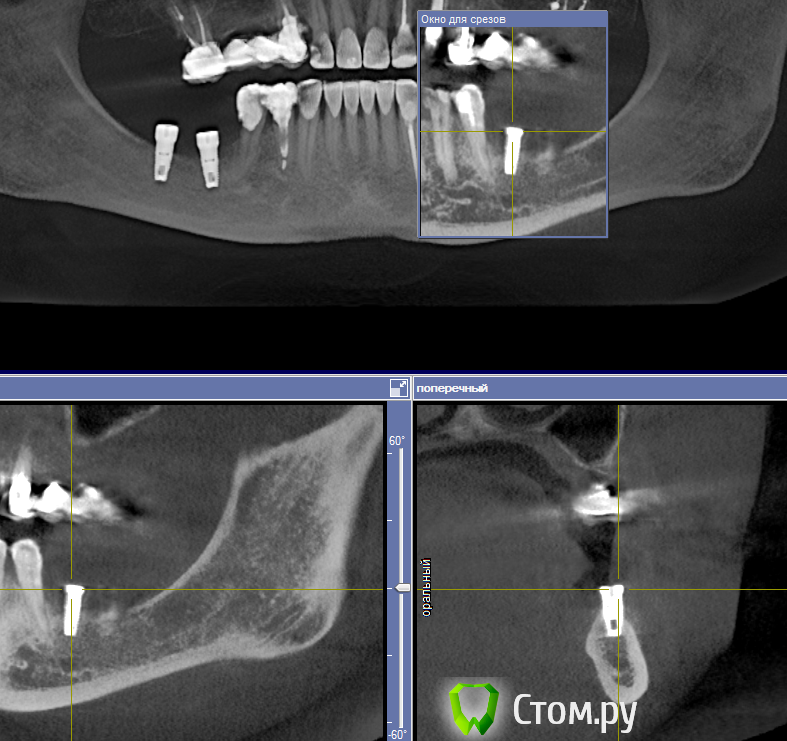

Libero15 Опубликовано 16 февраля, 2014 Поделиться Опубликовано 16 февраля, 2014 Подскажите, знающие люди, что за система??Заранее спасибо! Ссылка на комментарий

red_butler Опубликовано 16 февраля, 2014 Поделиться Опубликовано 16 февраля, 2014 2 red_butler: "А 3.7 Вас не смущает?"Я просто осторожен в своих выссказываниях, срезы на 3.7 не информативны. Система имплантов не знакома Ссылка на комментарий

Libero15 Опубликовано 16 февраля, 2014 Автор Поделиться Опубликовано 16 февраля, 2014 2 doc-евгенийимплантация была несколько лет назад. пока все стоит. Коллеги, просто нужно идентифицировать систему. Ссылка на комментарий

doca Опубликовано 16 февраля, 2014 Поделиться Опубликовано 16 февраля, 2014 Подскажите, знающие люди, что за система??Заранее спасибо!по глубокой шахте похож на нобель риплэйс Ссылка на комментарий

Libero15 Опубликовано 17 февраля, 2014 Автор Поделиться Опубликовано 17 февраля, 2014 может тогда уж уточнить у пациента,где,когда устанавливали?если не знает-связаться с лечащим врачом?устанавливали 2 года назад. клиника закрылась. связи с врачом никакой нет. пациентку уверили что это Анкилоз Ссылка на комментарий

Bier Опубликовано 17 февраля, 2014 Поделиться Опубликовано 17 февраля, 2014 По кт срезу имплант не определишь, сделайте орто или прицельный Ссылка на комментарий